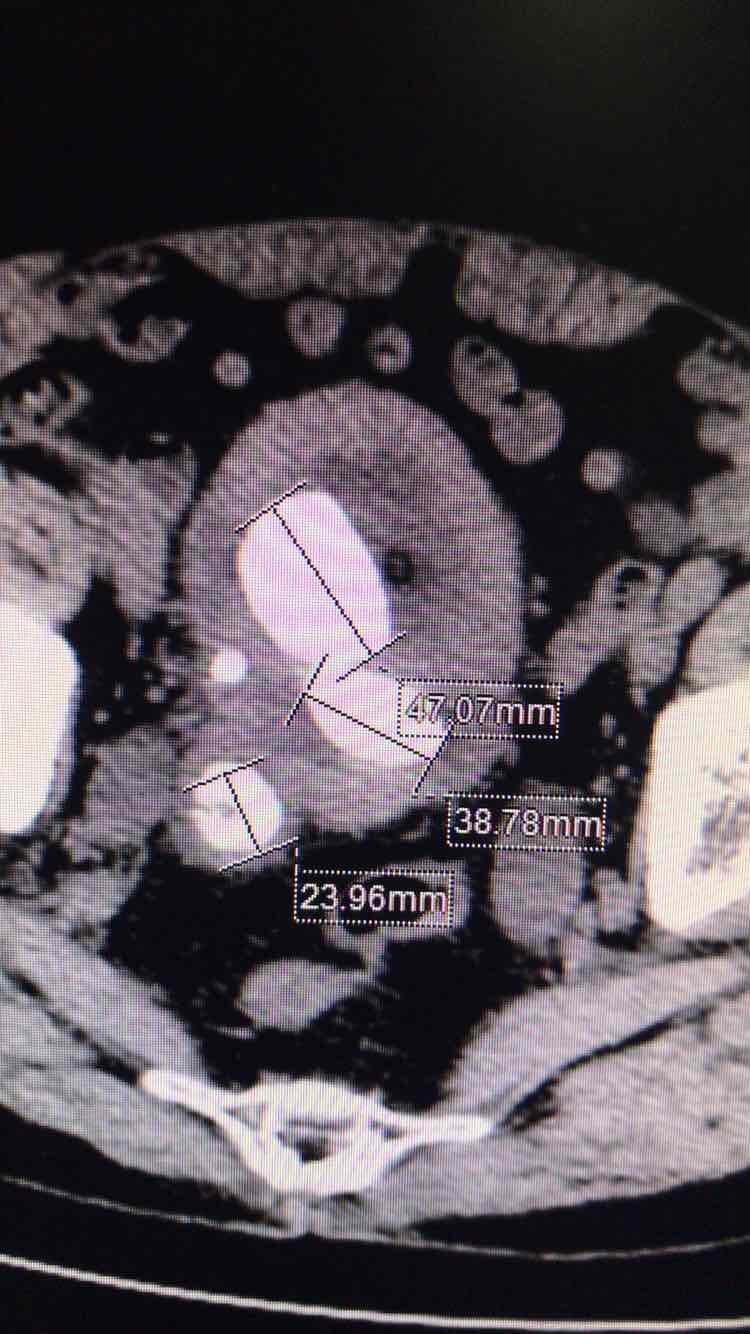

反复阅读ct均提示输尿管全程均匀,双肾重度积水,双侧输尿管结石,

双侧输尿管末端结石,膀胱多发结石

术中膀胱镜下未见输尿管开口,右侧见膀胱憩室一样的空腔,内见结石,结石跟术前阅片一致,术中处理膀胱结石。术后拟行双肾造瘘,术后结石未见,双肾积水明显减少,再来考虑原来双肾对称性重度积水为下尿路梗阻引起